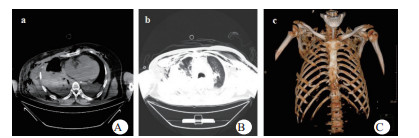

1 资料与方法患者,男,63岁,因“车祸致呼吸困难1 d”入院。既往体健。患者于2019年9月30日翻车致胸部挤压性创伤,伤后出现极度呼吸困难,送至当地医院,测血压80/50 mmHg(1 mmHg=0.133 kPa),胸部CT提示右侧血气胸,给予输血补液、去甲肾上腺素维持血压,经鼻气管插管呼吸机辅助通气,放置胸腔闭式引流管2根。因循环及氧合维持困难,10月1日转至徐州医科大学附属医院,收入EICU。入院查体:T 36.7℃,P 152次/min,R 14次/min(机械通气支持),BP 110/67 mmHg[去甲肾上腺素0.5 μg/kg·min)维持]。处于镇静状态,双侧瞳孔等大等圆,直径约2.0 mm,对光反射未引出;全身多处皮肤软组织擦挫伤,颈部及前胸、上肢广泛皮下气肿,右侧胸壁显著塌陷,反常呼吸,听诊双肺呼吸音低;心率快、心律齐、心音不遥远;腹部无异常体征;2根胸腔闭式引流管引流通畅。入院当天CT检查显示:双侧肋骨骨折伴右侧胸壁塌陷,两肺挫伤、创伤性湿肺,右肺撕裂伤,右侧液气胸,双侧胸壁广泛皮下气肿(图 1:A, B, C);未见颅内出血及腹部器官损伤。入室后0.5 h血气分析:pH 7.18,PCO2 57.5 mmHg,PO2 67.1 mmHg,Lac 4.4 mmol/L,氧合指数67.1 mmHg,APACHE Ⅱ评分27分。治疗上予镇痛镇静、保护性肺通气策略、保温、预防感染等治疗,效果不佳,连枷胸,皮下气肿范围不断扩大,氧合指数持续<100 mmHg。于10月2日气管切开后行V-V ECMO治疗(右股静脉—右颈静脉);因右侧血胸、胸引量24 h达1 000 mL,血红蛋白下降,凝血功能显著异常,存在创伤性凝血病,采取无肝素抗凝ECMO技术,提高血流速(4.6 L / min),气流速(5 L / min),FiO2 100%;给予成分输血,监测ACT及APTT。ECMO转机1h后去甲肾上腺素停用,复查血气分析PO2 105 mmHg。此后,患者氧合和血流动力学逐步改善,创伤性凝血病已纠正,于10月7日在无肝素V-V ECMO支持下行“胸骨骨折切开复位钢板内固定术+右侧3、4、5前肋肋骨骨折环抱器内固定+右侧5、6、7、8后肋肋骨骨折环抱器内固定术+两侧胸腔闭式引流术”。术中见第5肋骨前端骨折向下外移位,3、4肋骨多段骨折,胸壁前上方完全塌陷,肺脏直接外露,胸腔内布满血凝块,术中取出血凝块共约1 000 mL。术后氧分压上升至400 mmHg,术后复查床边胸片,肺部影像学较前改善(图 2 A, B),继续无肝素V-V ECMO治疗1 d后,于10月8日开始肝素抗凝,维持ACT在160 s~180 s,APTT在40 s~50 s,肝素化期间无出血并发症发生。10月11日行自主氧合试验通过,予以撤机。10月12日复查胸部CT两肺复张满意(图 3 A, B),开始间断停用呼吸机并床边康复训练。10月28日撤离呼吸机,气切处高流量吸氧。11月15日拔除气切管。11月18日康复出院,无明显并发症发生。

| 图 2 A入院第一天床边胸片;B术后当天床边胸片。 |